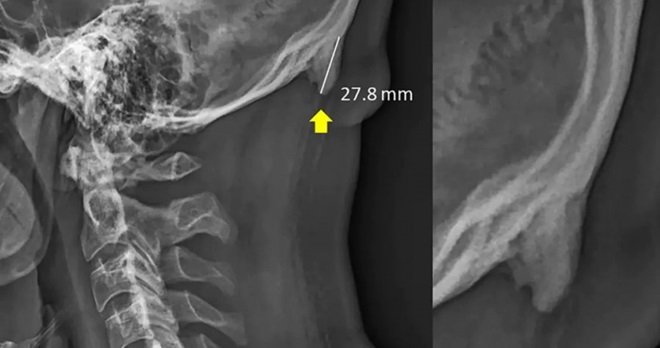

由于长期低头看屏幕,年轻人的头部骨骼后方出现了角状骨刺,这是身体用以支撑头部前倾重量的“进化反应”。

这篇论文的研究,基于218张X射线的样本,属于18到30岁之间的人群,当中有41%的人可观测到头部骨刺生长。